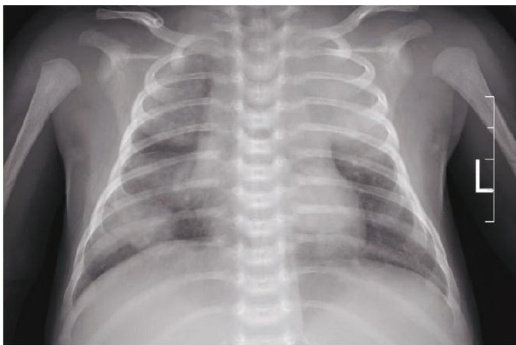

【关键词】新生儿;慢性X-连锁肉芽肿病;免疫缺陷34型;分枝杆菌感染;造血干细胞移植 中图分类号:R725.9 文献标志码:B DOI: 10.3969/j .issn.1003-1383.2026.01.016

新生儿慢性肉芽肿病(chronicgranulomatousdisease,CGD)由于其发病率较低且患儿缺乏明显的临床症状,常常在临床实践中被新生儿科医生忽视,从而导致治疗延误。(剩余7960字)

新生儿慢性X-连锁肉芽肿病合并免疫缺陷34型1例报道及文献复习